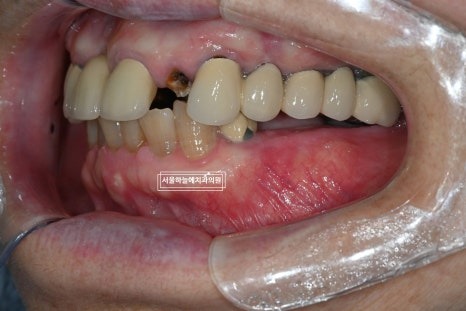

처음 내원 당시 엑스레이와 구강 상태를 보면

앞니는 파절되어 있었고

아래 어금니가 없는 기간이 길어

위 치아와 잇몸이 맞닿을 정도로 공간이 부족,

아래 앞니 역시 심하게 마모된 상태였습니다.

앞니 임플란트 & 당일 임시치아

부러진 앞니는 발치 후 임플란트 고정체를 식립하였고,

앞니는 심미적인 이유로 수술 당일 임시치아를 바로 장착해드렸습니다.